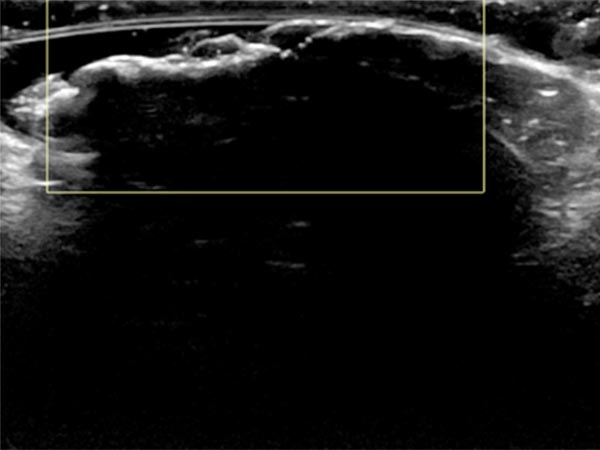

In sonography (B-scan), a total echo reflection with a pronounced acoustic shadow is found due to the high proportion of connective tissue on the surface of the nevus. The lesion itself cannot be visualized.

Color-coded duplex sonography also shows total echo reflection. No perfusion detectable even with a very sensitive setting for blood flow (6 cm/s).